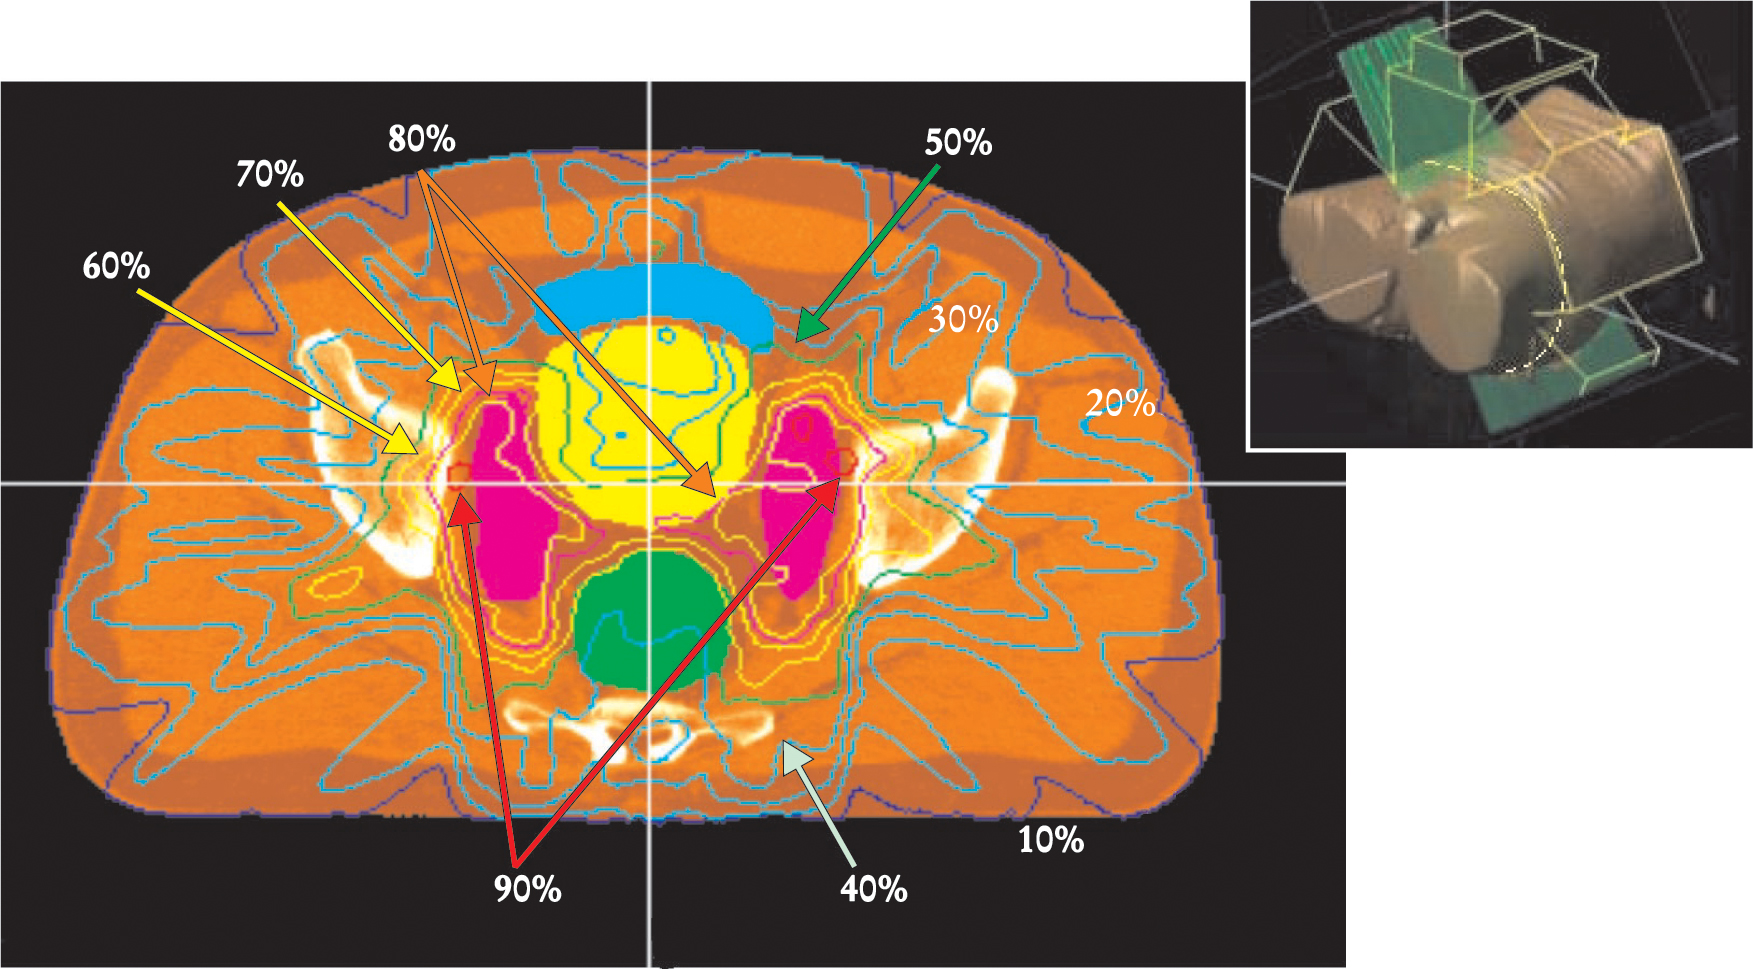

Visualizing 3D dose distributions is difficult. Within a 2D slice, however, isodose lines can be drawn through points of equal dose to characterize the dose distributions within a single plane. For example, figure 5 shows the dose distribution in a clinical application of IMRT for treating the prostate gland. The prostate is in a difficult position to treat with radiation. It is situated beneath and behind the bladder, an organ whose inner lining becomes inflamed at a radiation dose that depends partly on the area being exposed. The rectum, whose inner walls are particularly sensitive to radiation, lies immediately behind the prostate. Prostate cancer tends to spread along lymph vessels that radiate sideways from the prostate toward the walls of the pelvis and proceed up out of the pelvis into the abdomen, where they pass beside and in front of the sacrum, behind the large and small bowel, and up to the lower lumbar vertebrae. Irradiating this complex, inverted-Y volume while sparing the bowel, bladder, and rectum would not be feasible without IMRT. With IMRT, as figure 5 shows, the sensitive tissues can be largely avoided.13

IMRT dose delivery in the pelvis. Lines of constant x-ray dose of a prostate cancer treatment are displayed here over a section of a CT scan in the pelvis. The image plane, indicated by the yellow line in the inset, is viewed from below. The plane is above the prostate target but includes lymph nodes (purple), which are a route of spread of the cancer. The IMRT treatment concentrates the delivered dose onto the lymph nodes. The bladder (yellow) and the rectum (green), both organs at risk, receive a lower dose. The small bowel (blue) is also spared.